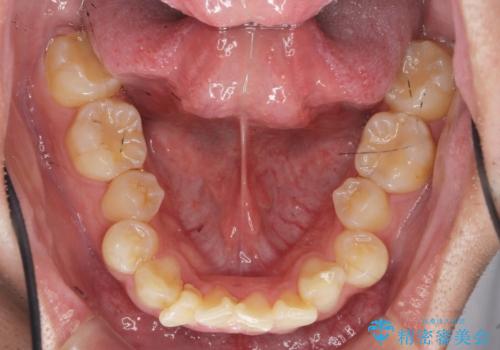

遠心移動を伴うマウスピース非抜歯矯正治療

- 「前歯の見た目を改善したい。」と矯正治療を希望され来院されました。

前歯のガタつきに加え、上顎が前にある咬合関係(上顎前突)を改善すべく、マイクロインプラントを用いた上顎奥歯の後方移動、拡大、ディスキングを用いたマウスピース矯正治療を計画します。

マイクロインプラントを使用したことで、しっかりと遠心移動が為され、良好な咬合関係が達成されました。